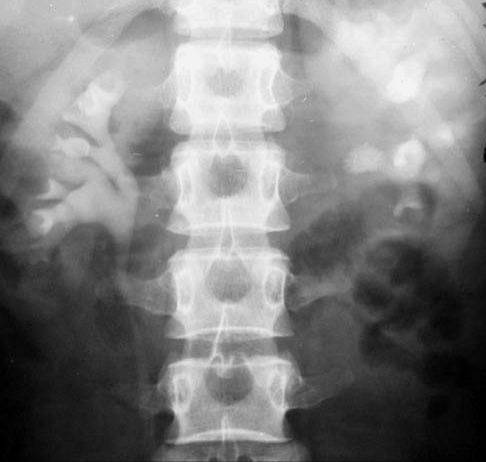

照片名称:肾性骨营养不良,cppd